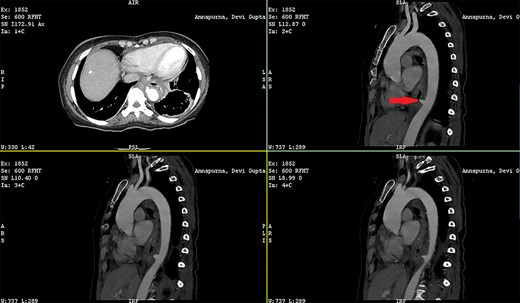

Patient 1: a 52-year-old woman, non-diabetic, non-hypertensive, was referred to the emergency with a history of large-volume, frank hematemesis (four episodes in 3 days). Positive history included recurrent cough for the past 1 year and low-grade fever for 3 months. No history of dysphagia, jaundice, abdominal distension, pain abdomen or altered sensorium. No history of chronic medications (oral anticoagulants or anti-platelets), analgesic intake or any substance abuse. She had received four units of packed red cells at an outside facility prior to admission. She was conscious, oriented, hemodynamically labile (heart rate: 110/min; BP: 86/60 mm Hg) with mild fever (99°F). General survey revealed obvious pallor. All other system examinations were within acceptable limits. Her hemoglobin (Hb) was 7.3 gram%, total leukocyte count (TLC) was 6400 cells/mm3, total bilirubin was 1.31 mg/dl and total protein was 4.75 gram%. An urgent UGI endoscopy revealed an opening in the posterior wall of the lower third of the esophagus, with a diverticulum. Inflammatory changes were noted in the diverticulum (Fig. 1). Contrast-enhanced computed tomogram (CECT) revealed erosion of the pouch into the thoracic aorta (Fig. 2), and a diagnosis of AEF with acute UGI hemorrhage was made.

CECT showing the descending thoracic aortic aneurysm; the red arrow shows the communication of the aneurysm with the esophagus.

Patient 2: a 48-year-old hypertensive, non-diabetic gentleman, presented to the emergency with one episode of massive hematemesis. There was no history of dysphagia, jaundice, abdominal distension, pain abdomen or altered sensorium. Past history was significant for percutaneous coronary intervention with two drug-eluting stents performed 3 years ago, for which he was on aspirin. He had normal mentation, his BP was 90/60 mm Hg and his heart rate was 120/min. A general survey revealed pallor and rest of the systemic examination was normal. His Hb was 6.1 gram% and TLC was 6300 cells/mm3. Liver function tests, coagulation parameters, renal function and electrolytes were normal. Chest X-ray was unremarkable. He was initially resuscitated with intravenous fluid, packed red blood cells and a proton-pump inhibitor infusion. An urgent UGI endoscopy revealed a large depressed ulcer with a red spot located in the middle third of the esophagus. A diverticulum was seen in the lower end of the ulcer (Fig. 7). An endoscopic clip was applied to the margin for ease of identification. CECT thorax revealed a 6 cm saccular thoracic aortic aneurysm distal to the left subclavian artery, eroding into the esophagus (Fig. 8).